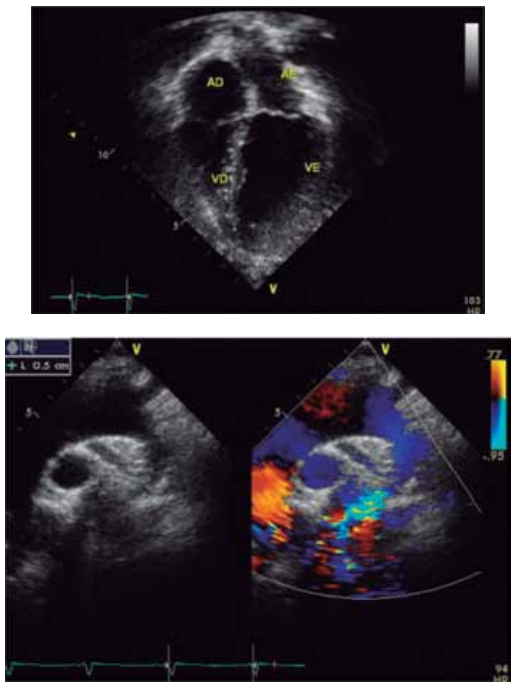

Considere as imagens a seguir.

(Arquivo pessoal; imagens usadas com autorização)

Qual é o diagnóstico provável da cardiopatia congênita ilustrada pela radiografia de tórax e a figura de ecocardiograma apresentadas desse recém-nascido?

Paciente de 1 mês de idade foi admitido em Unidade de

Terapia Intensiva, acompanhada de cuidadora de abrigo,

devido à piora da cianose. Mãe drogadita perdeu guarda

dos 6 filhos. A saturação na Unidade manteve-se estável,

ao redor de 84%, sem insuficiência cardíaca congestiva,

em uso de propranolol; foi acompanhado no ambulatório

até os 2 anos de idade e realizada intervenção cirúrgica

cardíaca. Com base nos seguintes exames complementares, quais seriam, sucessivamente, a cardiopatia congênita provável, a cirurgia realizada aos 2 anos de idade

e a cirurgia atual para a qual foi convocada?